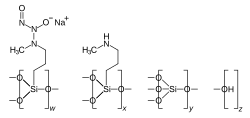

Berdazimer sodium

Berdazimer sodium, sold under the brand name Zelsuvmi, is a medication used for the treatment for molluscum contagiosum.[28] Berdazimer sodium is a nitric oxide releasing agent.[28] It is a polymer formed from sodium 1-hydroxy-3-methyl-3-(3-(trimethoxysilyl)propyl)-1-triazene-2-oxide and tetraethyl silicate.[29]

The most common side effects occurred at the drug application site including pain, rash, itch, eczema, swelling, erosion, discoloration, blister, irritation, and infection.[30] Other common side effects included fever, vomiting, and upper respiratory infections (common cold).[30]

Berdazimer sodium was approved for medical use in the United States in January 2024.[31][32][33] The US Food and Drug Administration (FDA) considers it to be a first-in-class medication.[34]Imiquimod